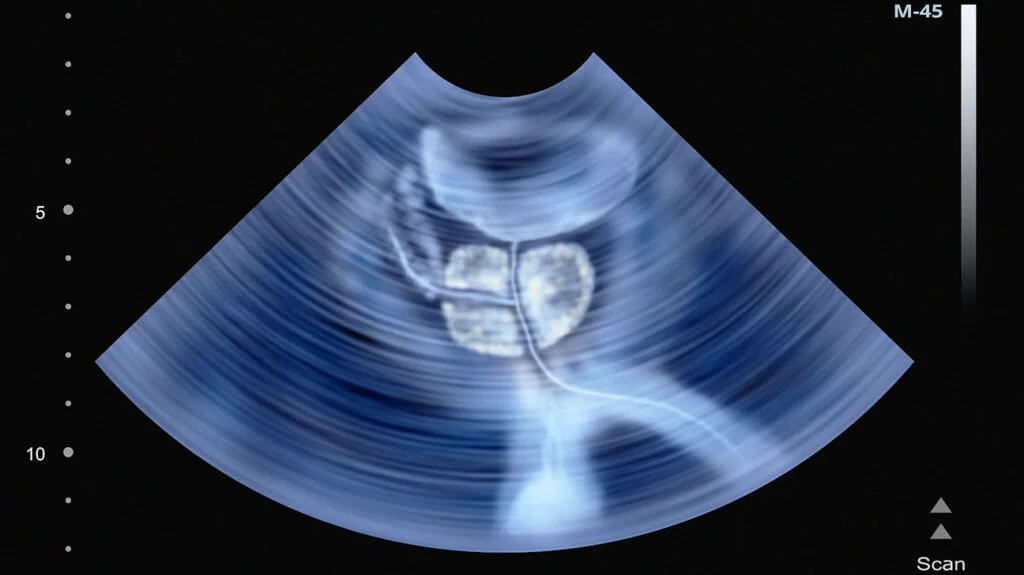

УЗИ предстательной железы – безопасное ультразвуковое исследование простаты, которое помогает выявить болезни репродуктивной системы у мужчин на бессимптомной стадии. Это важно, так как многие патологии протекают без видимых проявлений.

Процедура использует ультразвук для создания изображения органа без излучения, а значит без вреда для здоровья. Метод особенно актуален для мужчин старше 40 лет, когда растут онкологические риски. Диагностика занимает мало времени и не требует сложной подготовки. В медицинском центре доктора Бегмы используют современное оборудование для получения точных результатов.